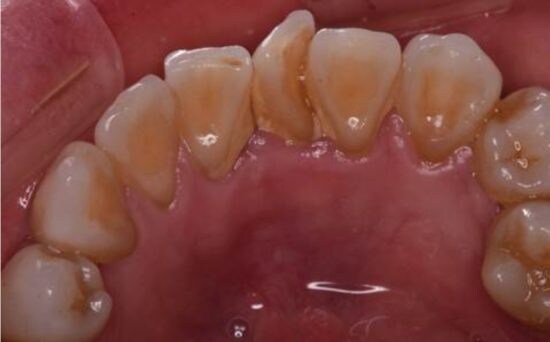

①歯石がたまりやすくなる……歯と歯の間に残った歯垢はやがて歯石となり、歯周病菌が繁殖しやすい環境をつくります。歯石があると歯周病はさらに進行しやすくなります。

実は、歯ブラシだけでは歯と歯の間の汚れ、つまりお口の中の汚れのおよそ40%を取りきれず、残ってしまうといわれています。歯科の現場において、「フロスや歯間ブラシを使っている人」と「使っていない人」の口内では、10年後に明確な差が出ているのが事実です。